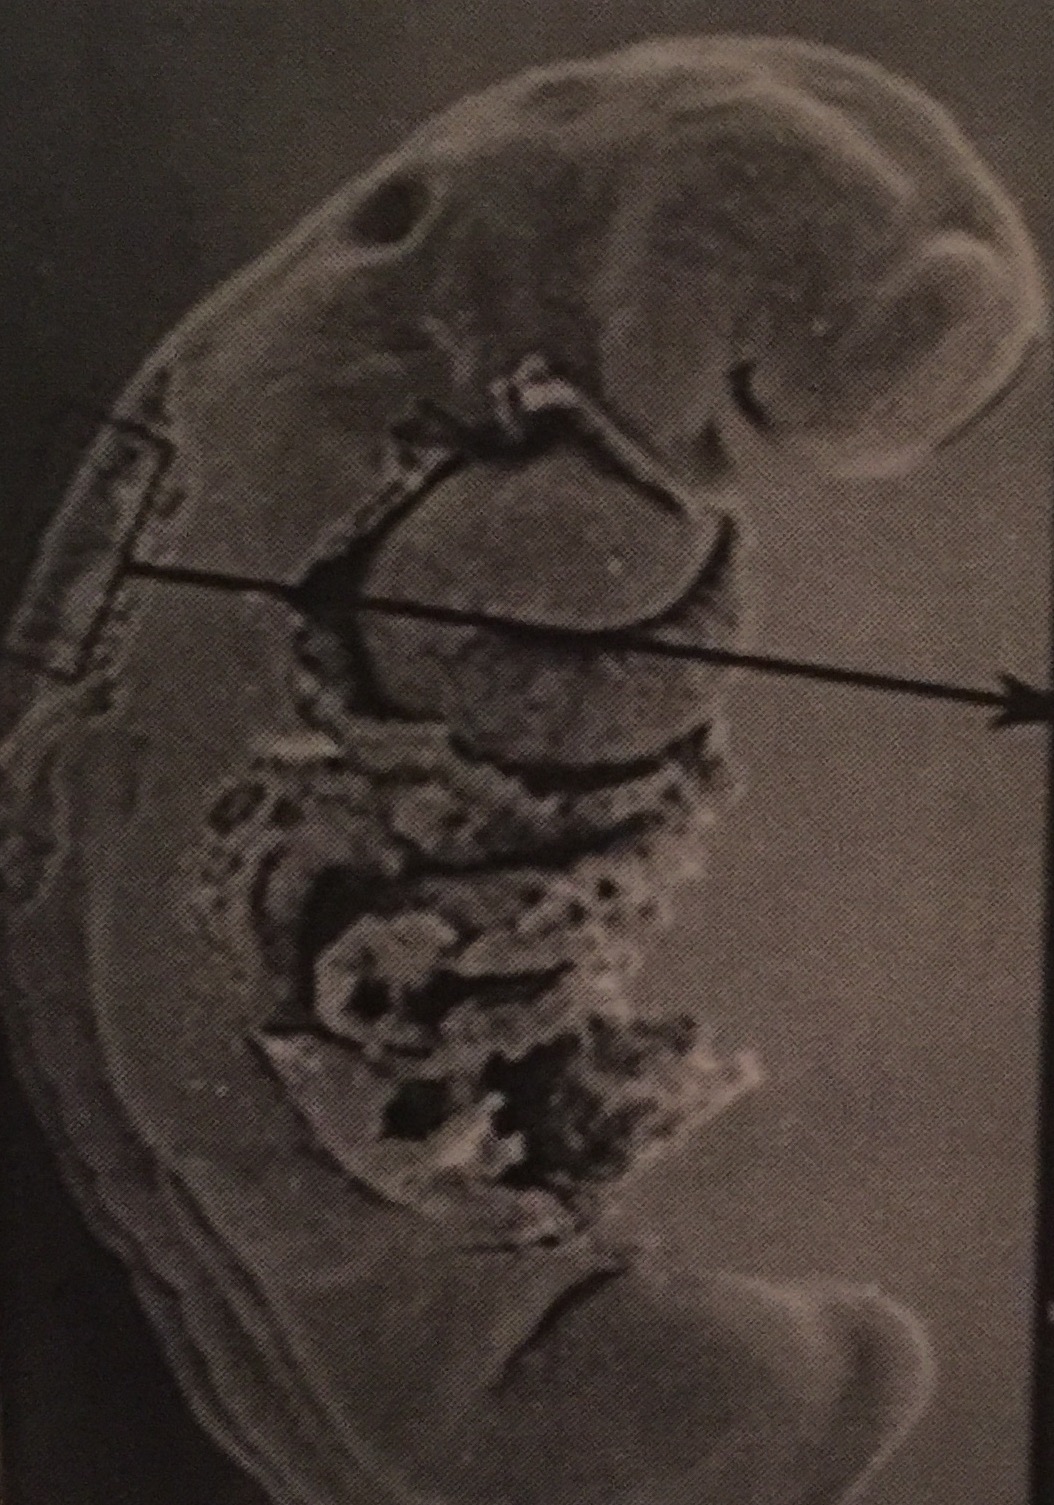

1)Ces 2 embryon appartiennent au même stade ? au stade 11 ?

Car on aperçoit bien le neuropore postérieur ouvert

Dans la fiche de carnegie de l'année dernière, cet embryon correspond au stade 12, peut être parce qu'on voit la placode otique ? Du coup je ne sais pas comment trancher ..